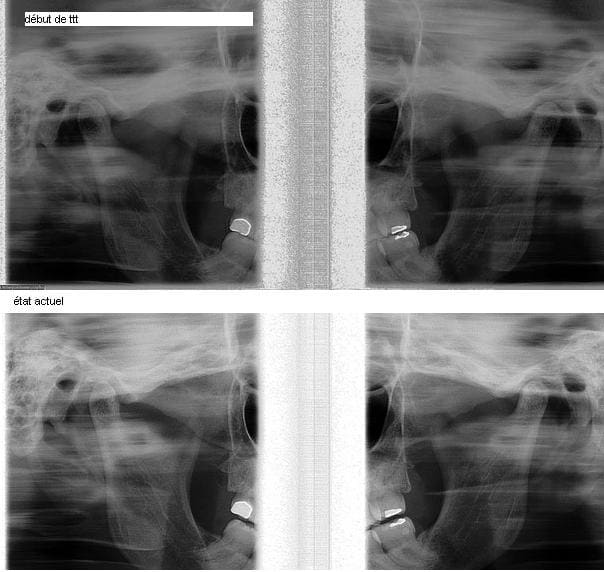

voici les photos; 3 semaines de Q.H.

la dérotation et la correction de constriction par redressement molaire ont entrainé

légère prop. Sup. ( c’est plutôt favorable)

une légère béance ( à contrôler, si je n’ai pas de réponse des 3/5°)

j’ai repris une tomo, par curiosité, pas de changements à G. c’aurait été trop beau

Voici les Rx. des ATM. de ma mamie prise vendredi

Je vous laisse juge

Elle revit …